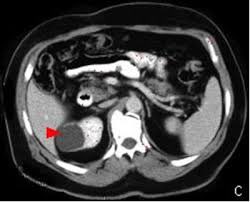

الاسباب :

غير معروفة ، الاصابة بارتفاع ضغط الدم ، قصور وظائف الكلى ، التقدم بالسن ، وفي حالات محدودة تكون باسباب وراثية او التهابات فطرية.

الاعراض : في الغالب بدون اعراض ، الم متقطع بالخاصرة او الجنب ، وفي حالات متقدمة ونادرة قد يكون دم بالبول